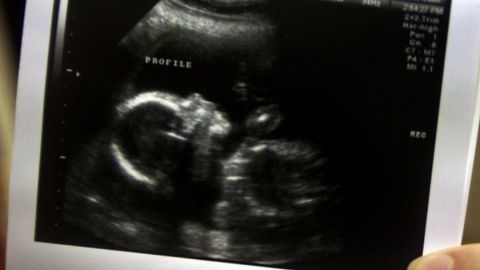

Cuando Brooke Barclay les contó a sus seguidores que tenía 20 semanas de embarazo, y mostró su ultrasonido, en redes sociales la tacharon de “mentirosa” y no faltó quien asegurara que estaba dando dicha declaración para llamar la atención y ganar más seguidores.